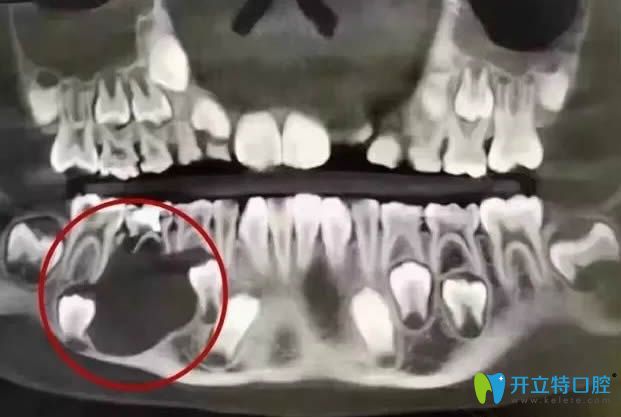

<這就是那位12歲小姑娘的口腔全景CT圖>

被切除下頜骨的口腔全景CT圖

許多家長仍在疑惑,乳牙出現(xiàn)問題是否會影響到孩子的恒牙生長?兒童乳牙出現(xiàn)蛀牙是否需要及時治療?實(shí)際上,乳牙損壞不僅會直接干擾恒牙的正常萌出,還會對頜骨的健康造成威脅!近期,一起在口腔醫(yī)療領(lǐng)域廣泛傳播的案例令人惋惜,受害者是一名12歲的女孩,由于乳牙蛀牙未得到妥善處理,最終引發(fā)了下頜部的大范圍囊腫,不得不接受下頜骨切除手術(shù),整個治療過程耗資高達(dá)16萬元,并且她的右側(cè)下頜骨失去了部分牙齒。